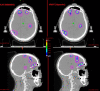

Purpose: Automated treatment planning systems are available for linear accelerator (linac)-based single-isocenter multi-target (SIMT) stereotactic radiosurgery (SRS) of brain metastases. In this study, we compared plan quality between Brainlab Elements Multiple Brain Metastases (Elements MBM) software which utilizes dynamic conformal arc therapy (DCAT) and Varian HyperArc (HA) software using a volumetric modulated arc therapy (VMAT) technique.

Patients and methods: Between July 2018 and April 2021, 36 consecutive patients ≥ 18 years old with 367 metastases who received SIMT SRS at UPMC Hillman Cancer San Pietro Hospital, Rome, were retrospectively evaluated. SRS plans were created using the commercial software Elements MBM SRS (Version 1.5 and 2.0). Median cumulative gross tumor volume (GTV) and planning tumor volume (PTV) were 1.33 cm3 and 3.42 cm3, respectively. All patients were replanned using HA automated software. Extracted dosimetric parameters included mean dose (Dmean) to the healthy brain, volumes of the healthy brain receiving more than 5, 8,10, and 12 Gy (V5Gy, V8Gy, V10Gy and V12Gy), and doses to hippocampi.

Results: Both techniques resulted in high-quality treatment plans, although Element MBM DCAT plans performed significantly better than HA VMAT plans, especially in cases of more than 10 lesions). Median V12Gy was 13.6 (range, 1.87-45.9) cm3 for DCAT plans and 18.5 (2.2-62,3) cm3 for VMAT plans (p < 0.0001), respectively. Similarly, V10Gy, V8Gy, V5Gy (p < 0.0001) and median dose to the normal brain (p = 0.0001) were favorable for DCAT plans.

Conclusions: Both Elements MBM and HA systems were able to generate high-quality plans in patients with up to 25 brain metastases. DCAT plans performed better in terms of normal brain sparing, especially in patients with more than ten lesions and limited total tumor volume.